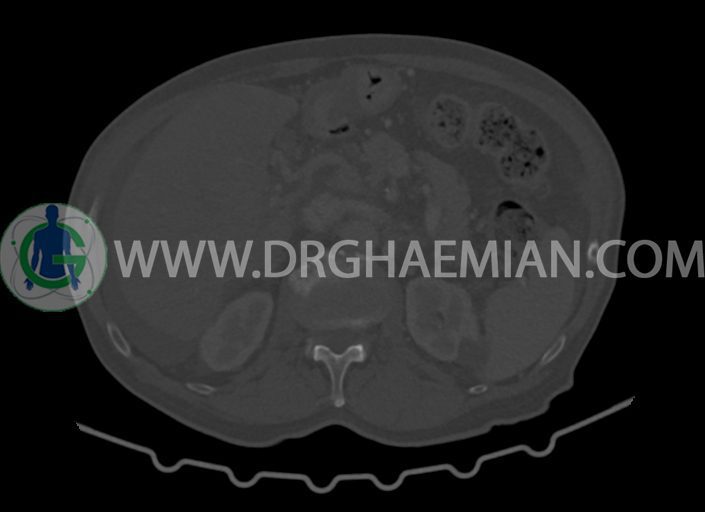

در سی تی اسکن اسپیرال شکم و لگن با کنتراست خوراکی و وریدی (مولتی دیدکتور 16 با مقاطع ظریف و بازسازی های ساژیتال و کرونال) :

-کیست های کورتیکال ساده در هر دو کلیه به بزرگترین قطر 27mm در سمت چپ (بوسنیاک 1)

–پروستات با دیامتر عرضی بزرگتر از نرمال 63mm همراه با بالجینگ به کف مثانه

-مثانه با جدار ضخیم و نامنظم

-ناحیه ی مشکوک به افزایش ضخامت جداری در کولون صعودی (نیازمند مطابقت کولونوسکوپی)